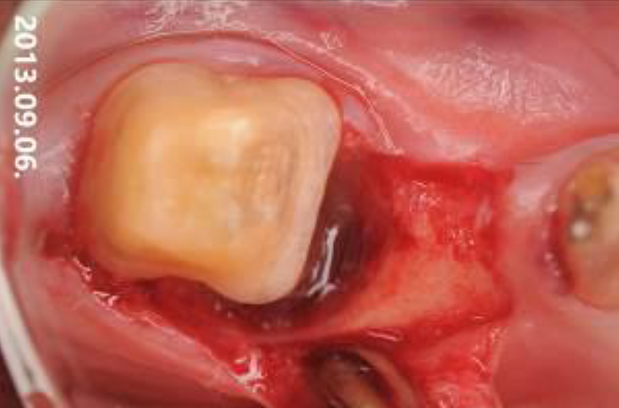

04/06 - Defect filled with small cerabone® granules.Intrabony defect treated using Straumann® Emdogain®, cerabone® and Jason® membrane - Dr. D. B. Hangyási